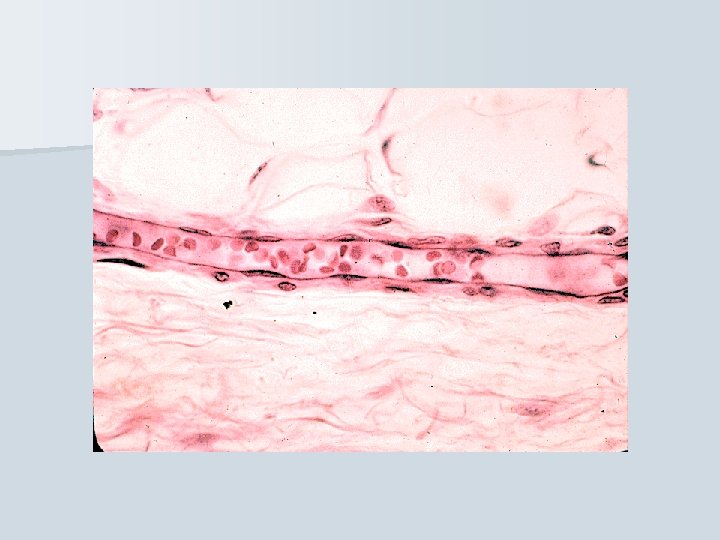

Blood capillaries Network of the smallest, thin- walled vessels, situated between arterial and venous portion of circuit

Blood capillaries n diameter from about 8 µm (to 30 -40 µm) n lumen is lined by 1 -2 endothelial cell n reticular fibers surround the capillaries n capillary bed between arteries and veins n pericytes 3 types of capillaries continuous fenestrated sinusoids

Continuous capillaries The smallest: cca 8 m n The wall: - endothelium – 1 -2 cells (zonulae occludentes and nexuses) - lamina basalis - pericytes - reticular fibers n n only allow small molecules, water and ions to diffuse Example of occurrence: muscle tisue, brain

Capillary